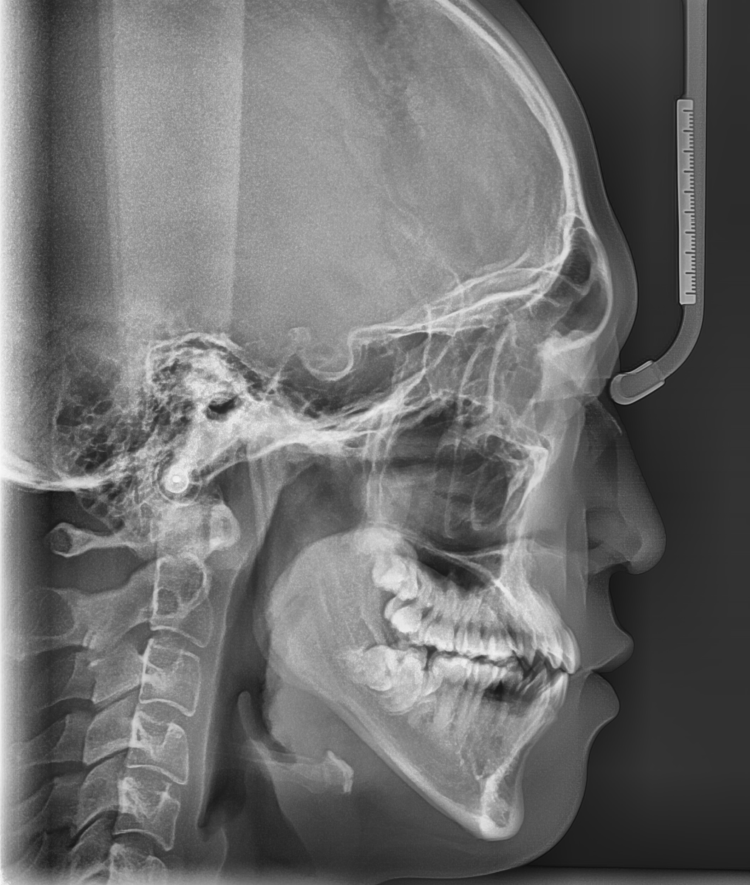

발치 여부는 환자의 치아 상태, 골격 구조, 교합 상태

복합적으로 고려하여 결정해야해요~

정확한 진단을 위해 X-RAY와 구강 내 사진을 많이 찍게 되는데

환자분들께 조금 힘드시더라도

만족스러운 교정을 위한 과정이니 양해 부탁드립니다!!!